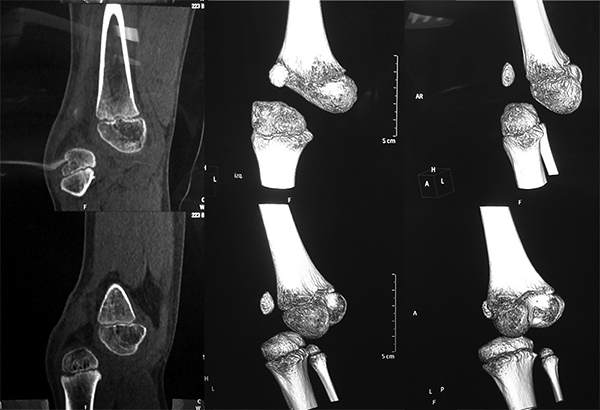

Los estudios radiológicos confirmaron el diagnóstico clínico (figs. 4 y 5). Se decidió el tratamiento quirúrgico de la luxación femorotibial de su rodilla derecha.

Figura 5: Imágenes tomográficas que confirman luxación anterior femorotibial.